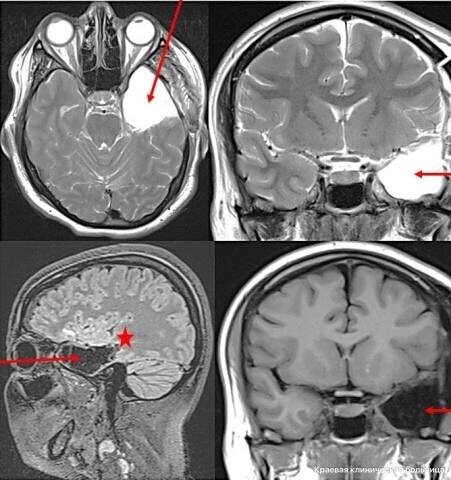

В Красноярске состоялась уникальная операция по удалению части головного мозга у пациентки в сознании. Это первый опыт такого рода в регионе.

Хирурги краевой клинической больницы применили инновационный подход, временно выводя пациентку из наркоза во время операции, чтобы оценить сохранность речевых функций.

29-летняя пациентка долгое время страдала от тяжелой эпилепсии, испытывая до восьми приступов в день, которые не поддавались лечению лекарствами.

После удаления части височной доли мозга и гиппокампа приступы полностью прекратились. Речевые способности пациентки остались полностью сохранены, а общее состояние здоровья улучшилось.